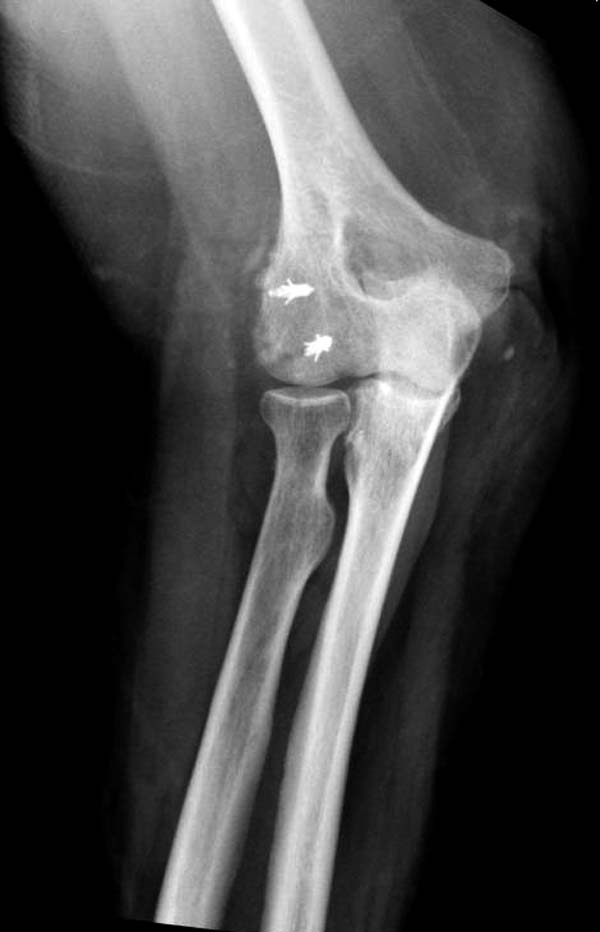

В данном случае имеется, так называемая, "ужасная триада" локтевого сустава, включающая перелом головки лучевой кости, перелом венечного отростка и вывих костей предплечья кзади, также в структуру травмы входит повреждение латерального коллатерального связочного комплекса и возможно передней порции медиальной коллатеральной связки. Лечение состоит из следующих этапов: фиксация венечного отростка( анкер или проволочная петля типа лассо), далее остеосинтез или протезирование головки лучевой кости ( КТ было бы желательно, фотографии не особо четкие), затем шов латерального коллатерального связочного комплекса. Если сохранится нестабильность, потребуется или шов передней порции медиальной коллатеральной связки с иммобилизацией верхней конечности аппаратом внешней фиксации (желательно с сохранением движений в локтевом суставе) или только аппарат(мнения расходятся). Аппарат 6 недель. Результаты лечения таких повреждений не очень хорошие.

Для примера здесь случай начатый в другом центре, а потом переправленный к нам.

Снимки: 1-2 вывих, 4-5 вторичное смещение в гипсе, реконструкция латеральной связки и капсулы 13-14, повторный вывих после реконструкции, перевод в наш центр; 18-21 временная фиксация, 22-25 трансартикулярная фиксация и нестабильная головка фиксирована спицами, 29-30 амбулаторно, 32-33 после удаления винта и спиц...